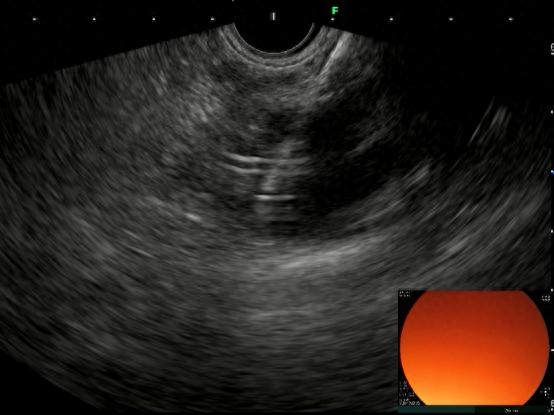

超声引导下细针穿刺